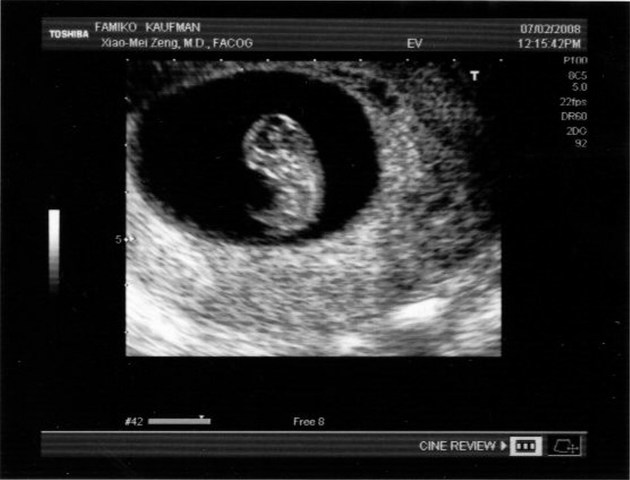

• Blastocito

Blastocito

Fase del desarrollo del embrión de los mamíferos, equivalente a la blástula, que constituye una estructura celular compleja derivada de la mórula; está formada por una masa celular interna de la que se origina el embrión y de una capa periférica de células que formará la placenta.

• ANIDACION

ANIDACION

La implantación comienza al final de la primera semana -séptimo u octavo día- después de la fecundación del óvulo por el espermatozoide y se extiende hasta el final de la segunda semana -14 días después de la fecundación.